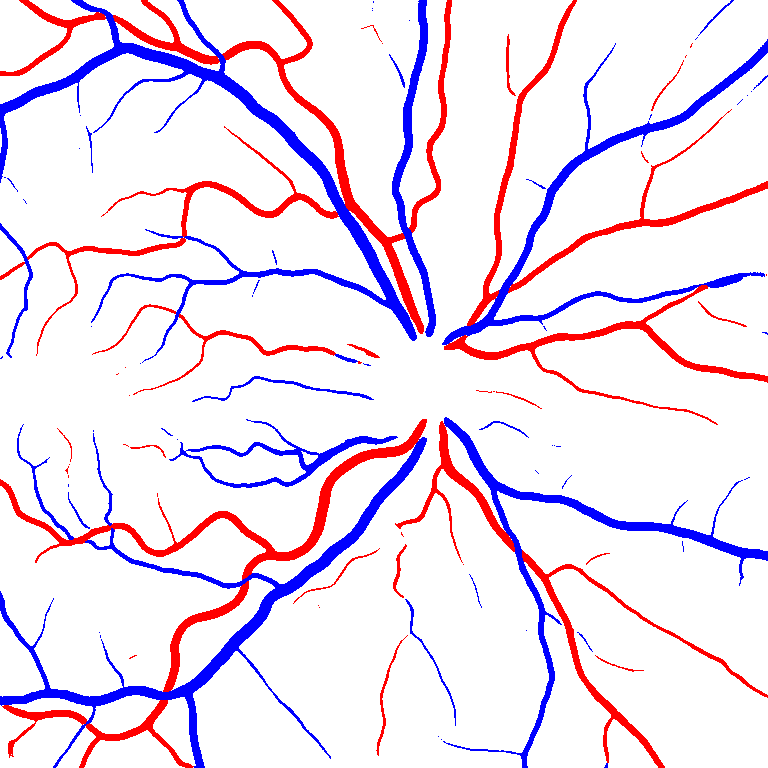

Table V presents quantitative performance benchmarks of SegRAVIR and other competing approaches for retinal artery and vein classification on the RITE dataset [11]. SegRAVIR outperforms previous state-of-the-art approaches in terms of accuracy, sensitivity, and specificity. Fig. 5 provides a qualitative comparison between segmentation outputs of SegRAVIR and the method of Hemelings et al. [40] on the RITE test set.